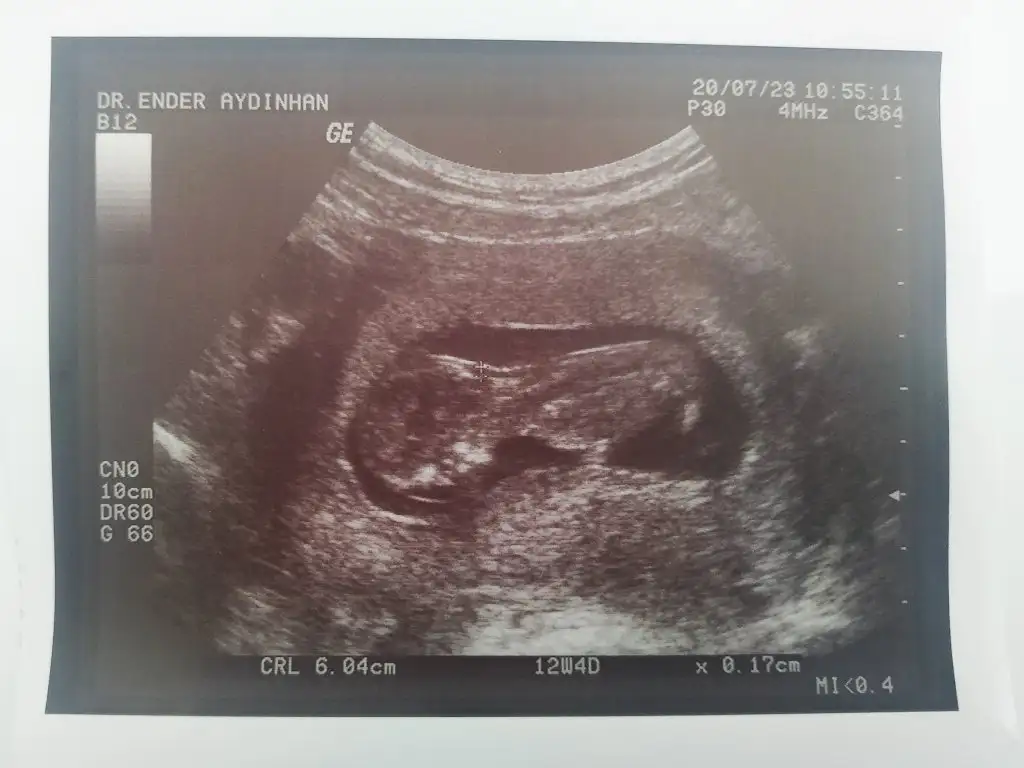

9. 10. Haftalarda hep kız gibi dediniz bakalım bu sefer ki fikriniz ne olacak şimdiden teşekkür ediyorum sevgiler❤Eki Görüntüle 2666654

Bunada bakarmisiniz 12 haftalikKız gibi sanki

Kız sankiBunada bakarmisiniz 12 haftalik Eki Görüntüle 2666679

Doktorda kiza benzetti ama tm emin olamadi bidaha cagirdi 18gun sonra gitcemKız sanki

Kaç haftalık sanki erkek gibi emin olamadımSizce nub a göre ne ? Eki Görüntüle 2667004